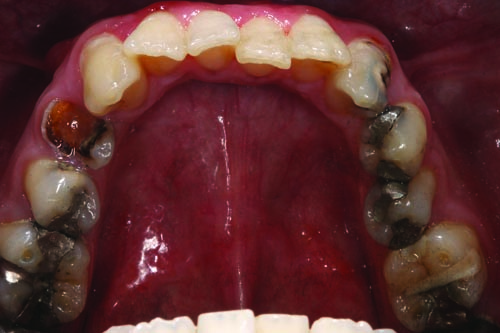

Fig. 4: The preoperative left lateral view reveals that any treatment undertaken should address the patient’s numerous missing teeth, including #12, #15, #16 and #17 and multiple MOD amalgam restorations on teeth #13, #14 and #18 through #21.

Fig. 7: Palatal view of the maxillary arch revealing the distal/lingual (DL) composite restorations on teeth #9 and #11.